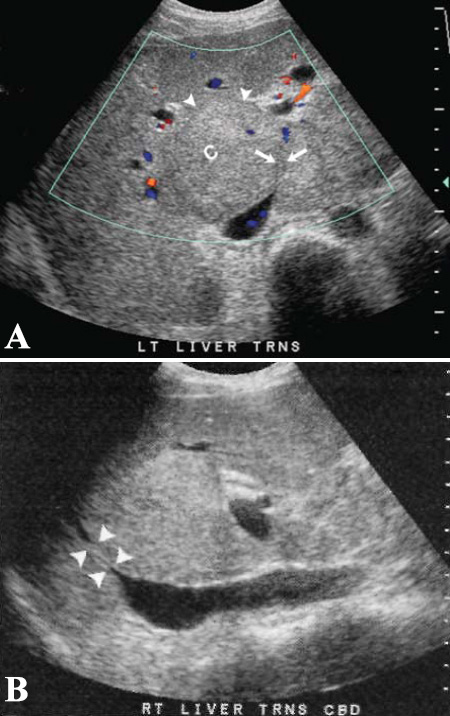

Фото 6. Синдром Бадда-Киари. А – поперечное изображение на уровне нижней полой вены: стрелками обозначено сужение печеночной вены (цветовая допплерография) и увеличение хвостатой доли печени (см указатели). В – продольное изображение правой доли печени: указателями отмечено значительное сужение нижней полой вены